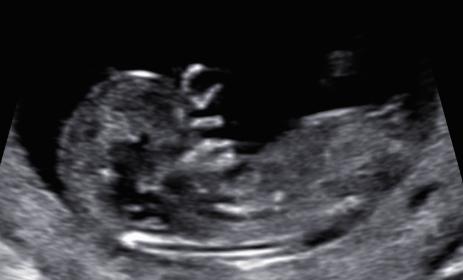

This is really early 11w3d but thought id throw it out there. During the scan i thought i saw a girl nub but didnt get a pic of it.

I don't know how to read skulls but nub wise its looking feminine. :)

Both boy and girl nubs look the same/girly at this gestation so wouldn't take a guess. Best time for nub guessing is from mid 12 weeks until 14 weeks.

Too early. Both sexes look the same at this gestation.